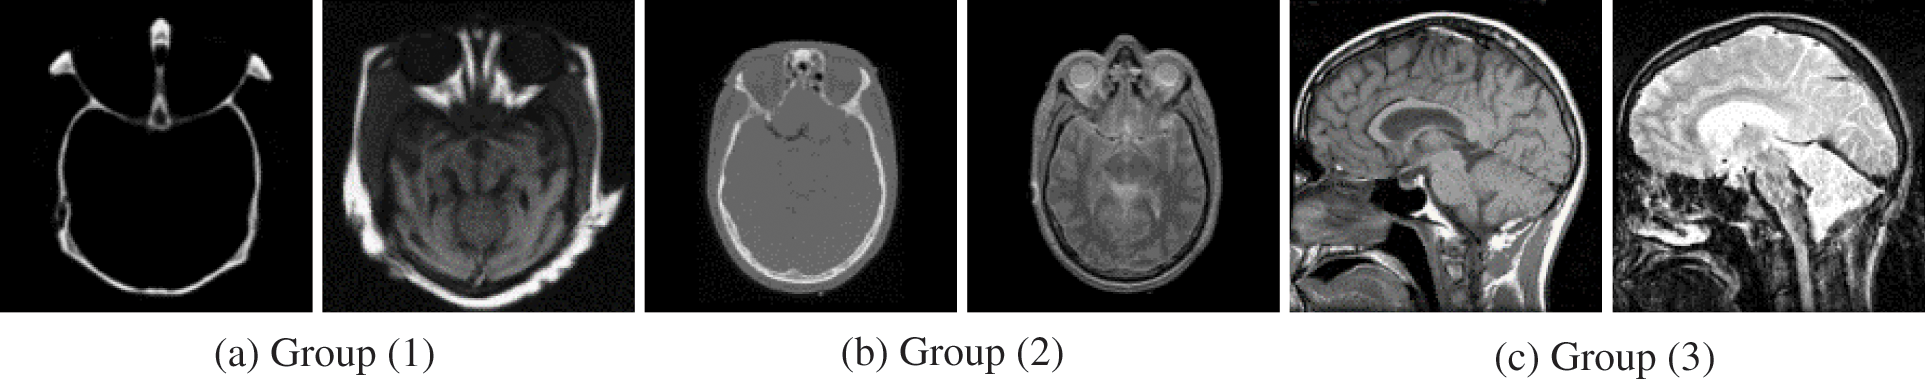

This study presents experimental results on three pairs of 256 × 256 registered medical images from three different modalities due to space limitations to show the efficiency of the proposed technique for fusing medical images. Three sets of CT and MRI images (Groups 1–3) are utilized in the experiments. All of the input images are selected from the Harvard Medical School website [40] and demonstrated in Fig. 2. The appropriate experimental findings and discussions are illustrated in detail. Nine representative image fusion algorithms including “Wasserstein generative adversarial networks (WGAN) [30], a weighted parameter adaptive dual-channel PCNN (WPADC-PCNN) [29], Laplacian pyramid and adaptive sparse representation (LP-ASR) [17], Geometric algebra discrete cosine transform (GA-DCT) [22], Image fusion using saliency capturing (IF-SC) [8], L0 gradient minimization (LGM) [19], Hybrid approach of NSCT and DTCWT (NSCT-DTCWT) [23], Multimodal brain medical image fusion based on the improvement of a generative adversarial network (MMFGAN) [33] and Multiscale residual pyramid attention network (MRPAN) [31]”. The default values of the parameters were taken for the above-mentioned fusion methods which are stated in each of the publications.

Figure 2: Source image pairs of multimodal medical images [40]. In (a–c), three pairs of CT and MRI images. Left: CT image; right: MRI image